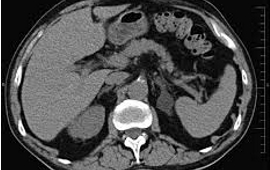

¿Qué patología identifica el signo del arco vascular?

Osteoporosis - Hiperaldosteronismo primario - Neoplasia endocrina múltiple tipo 1 - Incidentaloma adrenal